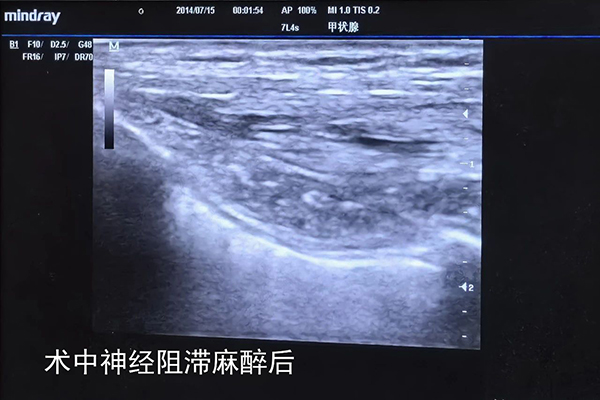

手术由普外科副主任医师李华志和主治医师佟凡携手完成。鉴于患者体型瘦弱,加之左乳肿瘤已逾一年未接受治疗,其直径已增至5厘米。麻醉科主治医师杜鹃在术前为患者量身定制了神经阻滞麻醉方案。得益于手术团队的高超技艺与完美协作,患者顺利完成了根治性手术,并在术后第二天顺利出院。

▲患者术中神经阻滞麻醉前后对比